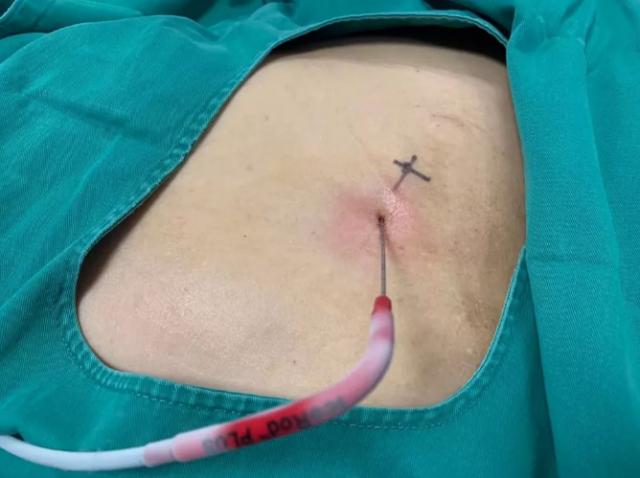

2017年9月29日,從CT影像看到右腎情況更為嚴重。為減緩腫瘤增長的速度,專家進行商議后,最終決定由牛立志教授主刀為安圖叔叔進行了右腎腫瘤冷凍消融術。手術開始后,牛立志教授在CT和超聲引導下,同時使用兩根冷凍針固定病灶,精準滅活腫瘤;術后很成功無不良反應。術后一周進行第二次雙腎腫瘤冷凍消融術。安圖叔叔兒子笑道:“當時真的很緊張,醫(yī)生勸慰我無須擔心,都交給他們,我們都很清楚知道父親的病情,真的很感謝也很慶幸我父親遇到復大的醫(yī)護人員,免受開刀之痛。住院期間醫(yī)護人員很盡心盡力的照顧父親,手術的成功離不開他們的辛勞付出!

冷凍治療手術中